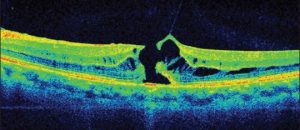

La tomografia a coerenza ottica (OCT) è un test di imaging non invasivo che utilizza le onde di luce per scattare foto della retina, e in particolare della macula. La macula è una parte della retina deputata alla visione a colori e ad alta definizione.

Con l’OCT possono essere analizzati e mappati tutti gli strati retinici, inoltre è possibile rilevare lo spessore retinico. Questi dati aiutano a effettuare una corretta diagnosi e a fornire delle indicazioni per il trattamento del glaucoma e delle patologie retiniche, malattie come la degenerazione maculare senile e la retinopatia diabetica.

Se in atto è presente o è stata presente una di queste condizioni retiniche è importante eseguire l’OCT.